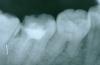

victory5 Опубликовано 21 марта, 2008 Поделиться Опубликовано 21 марта, 2008 Здравствуйте, помогите советом. Врач сказала, что после перепломбирования вероятность потери зуба остается, только через год можно увидеть приживется или нет. Подскажите, пожалуйста, можно ли сделать зуб наверняка!? Не хочется терять зуб... Прикреплён один снимок в двух вариантах сканирования... Ссылка на комментарий

АНРОША Опубликовано 21 марта, 2008 Поделиться Опубликовано 21 марта, 2008 Качество снимка оставляет желать лучшего... 100% гарантию на перелечивание каналов Вам не даст никто. Всегда остается риск возникновения воспаления. По Вашему снимку можно сказать, что все не так ужасно . При качественно проведенном эндодонтическом лечении скорее всего зуб "приживется" Ссылка на комментарий

NataLee Опубликовано 21 марта, 2008 Поделиться Опубликовано 21 марта, 2008 Здравствуйте, помогите советом. Врач сказала, что после перепломбирования вероятность потери зуба остается, только через год можно увидеть приживется или нет. Подскажите, пожалуйста, можно ли сделать зуб наверняка!? Не хочется терять зуб... Прикреплён один снимок в двух вариантах сканирования...Не вижу ничего криминального. Вероятность потери зуба есть всегда. Но попробовать стОит. При качественном повторном лечении каналов у зуба есть все шансы жить ещё долго и счастливо Ссылка на комментарий

Палыч Опубликовано 22 марта, 2008 Поделиться Опубликовано 22 марта, 2008 Здравствуйте, помогите советом. Врач сказала, что после перепломбирования вероятность потери зуба остается, только через год можно увидеть приживется или нет. Подскажите, пожалуйста, можно ли сделать зуб наверняка!? Не хочется терять зуб... Прикреплён один снимок в двух вариантах сканирования... Не понятно, где и у кого должен прижиться Ваш зуб. По моему ему и на своем месте не плохо живется. Вернее буде сказать, существуется, т.к. он (зуб) уже не живой. А перспектива перелечивания, насколько можно судить по данному снимку, достаточно прогнозируема и реальна. Ссылка на комментарий

Selena Опубликовано 22 марта, 2008 Поделиться Опубликовано 22 марта, 2008 Из того, что можно рассмотреть на данном снимке - все не так плохо, главное - качественное лечение должно быть с обязательным рентгенконтролем на каждом этапе и окончательным снимком, желательно цифровые снимки проводить Ссылка на комментарий